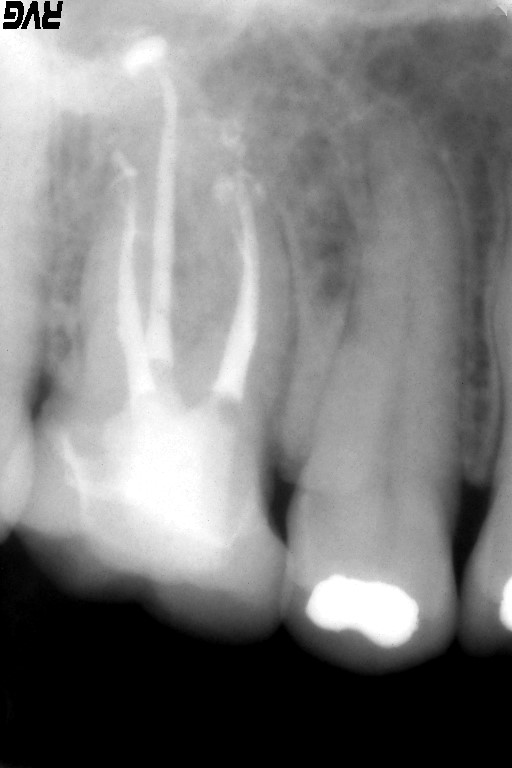

術前のレントゲン:近心頬側根に炎症があるように観えます。

根管の先、根尖を確認するためにファイルを入れた状態でレントゲンを撮り、根管の長さや根尖孔の太さや状態を確認しています。

根管充填後のレントゲン写真。根管の複雑な解剖学形態にきちんとガッタパーチャが根管充填されている事が確認できます。